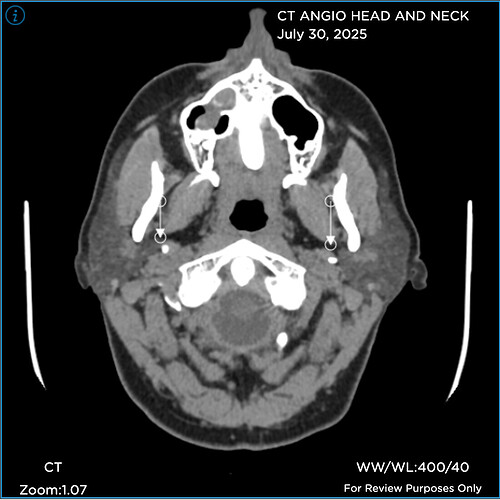

Hi folks. Like many of you, I’ve been on a miserable journey for years now. I’m just diagnosed “officially” with Eagles yet, but my provider said she sees elongated styloids on both sides, and she has referred me to Hepworth and recommends styloidecomy(ies).

Prior to seeing her, I’d been dealing with a CSF leak (5 blood patches to date), chronic migraines, Central Sensitization Syndrome/fibro (basically whole body pain), etc. When my FMC looked at the imaging I finally uploaded, she immediately noticed elongated styloids on both sides and she recommends styloidectomy(ies).